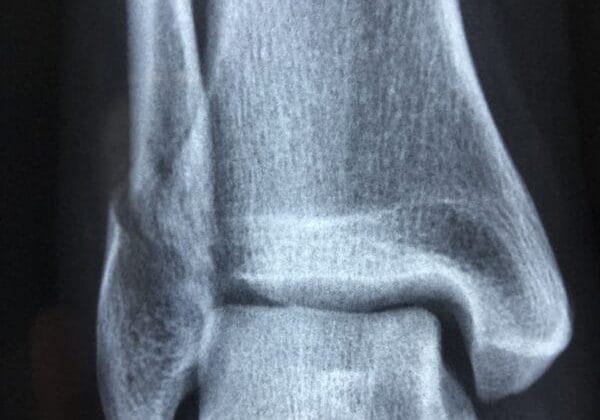

The rehabilitation process for injured NBA players is multifaceted and often involves a team of medical professionals working collaboratively to ensure optimal recovery. Initially, after an injury occurs, immediate assessment is crucial to determine the extent of damage and develop an appropriate treatment plan. This may include imaging studies such as MRIs or X-rays to provide a clearer picture of the injury’s severity.

Once a diagnosis is established, rehabilitation typically begins with a focus on pain management and restoring mobility. Physical therapists play a vital role in guiding players through exercises designed to strengthen affected areas while gradually increasing range of motion. For example, after an ACL tear, a player may start with gentle range-of-motion exercises before progressing to more intensive strength training as healing occurs.